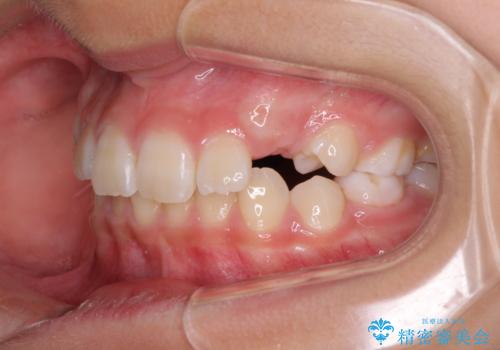

- 小学校での定期歯科検診にて歯列不正を指摘されたとのことで来院された患者様です。

左上の犬歯が低位に埋伏しており、将来八重歯になるリスクが高いと判断されたため、補助装置とワイヤーを用いて犬歯を通常の位置まで移動させることとしました。